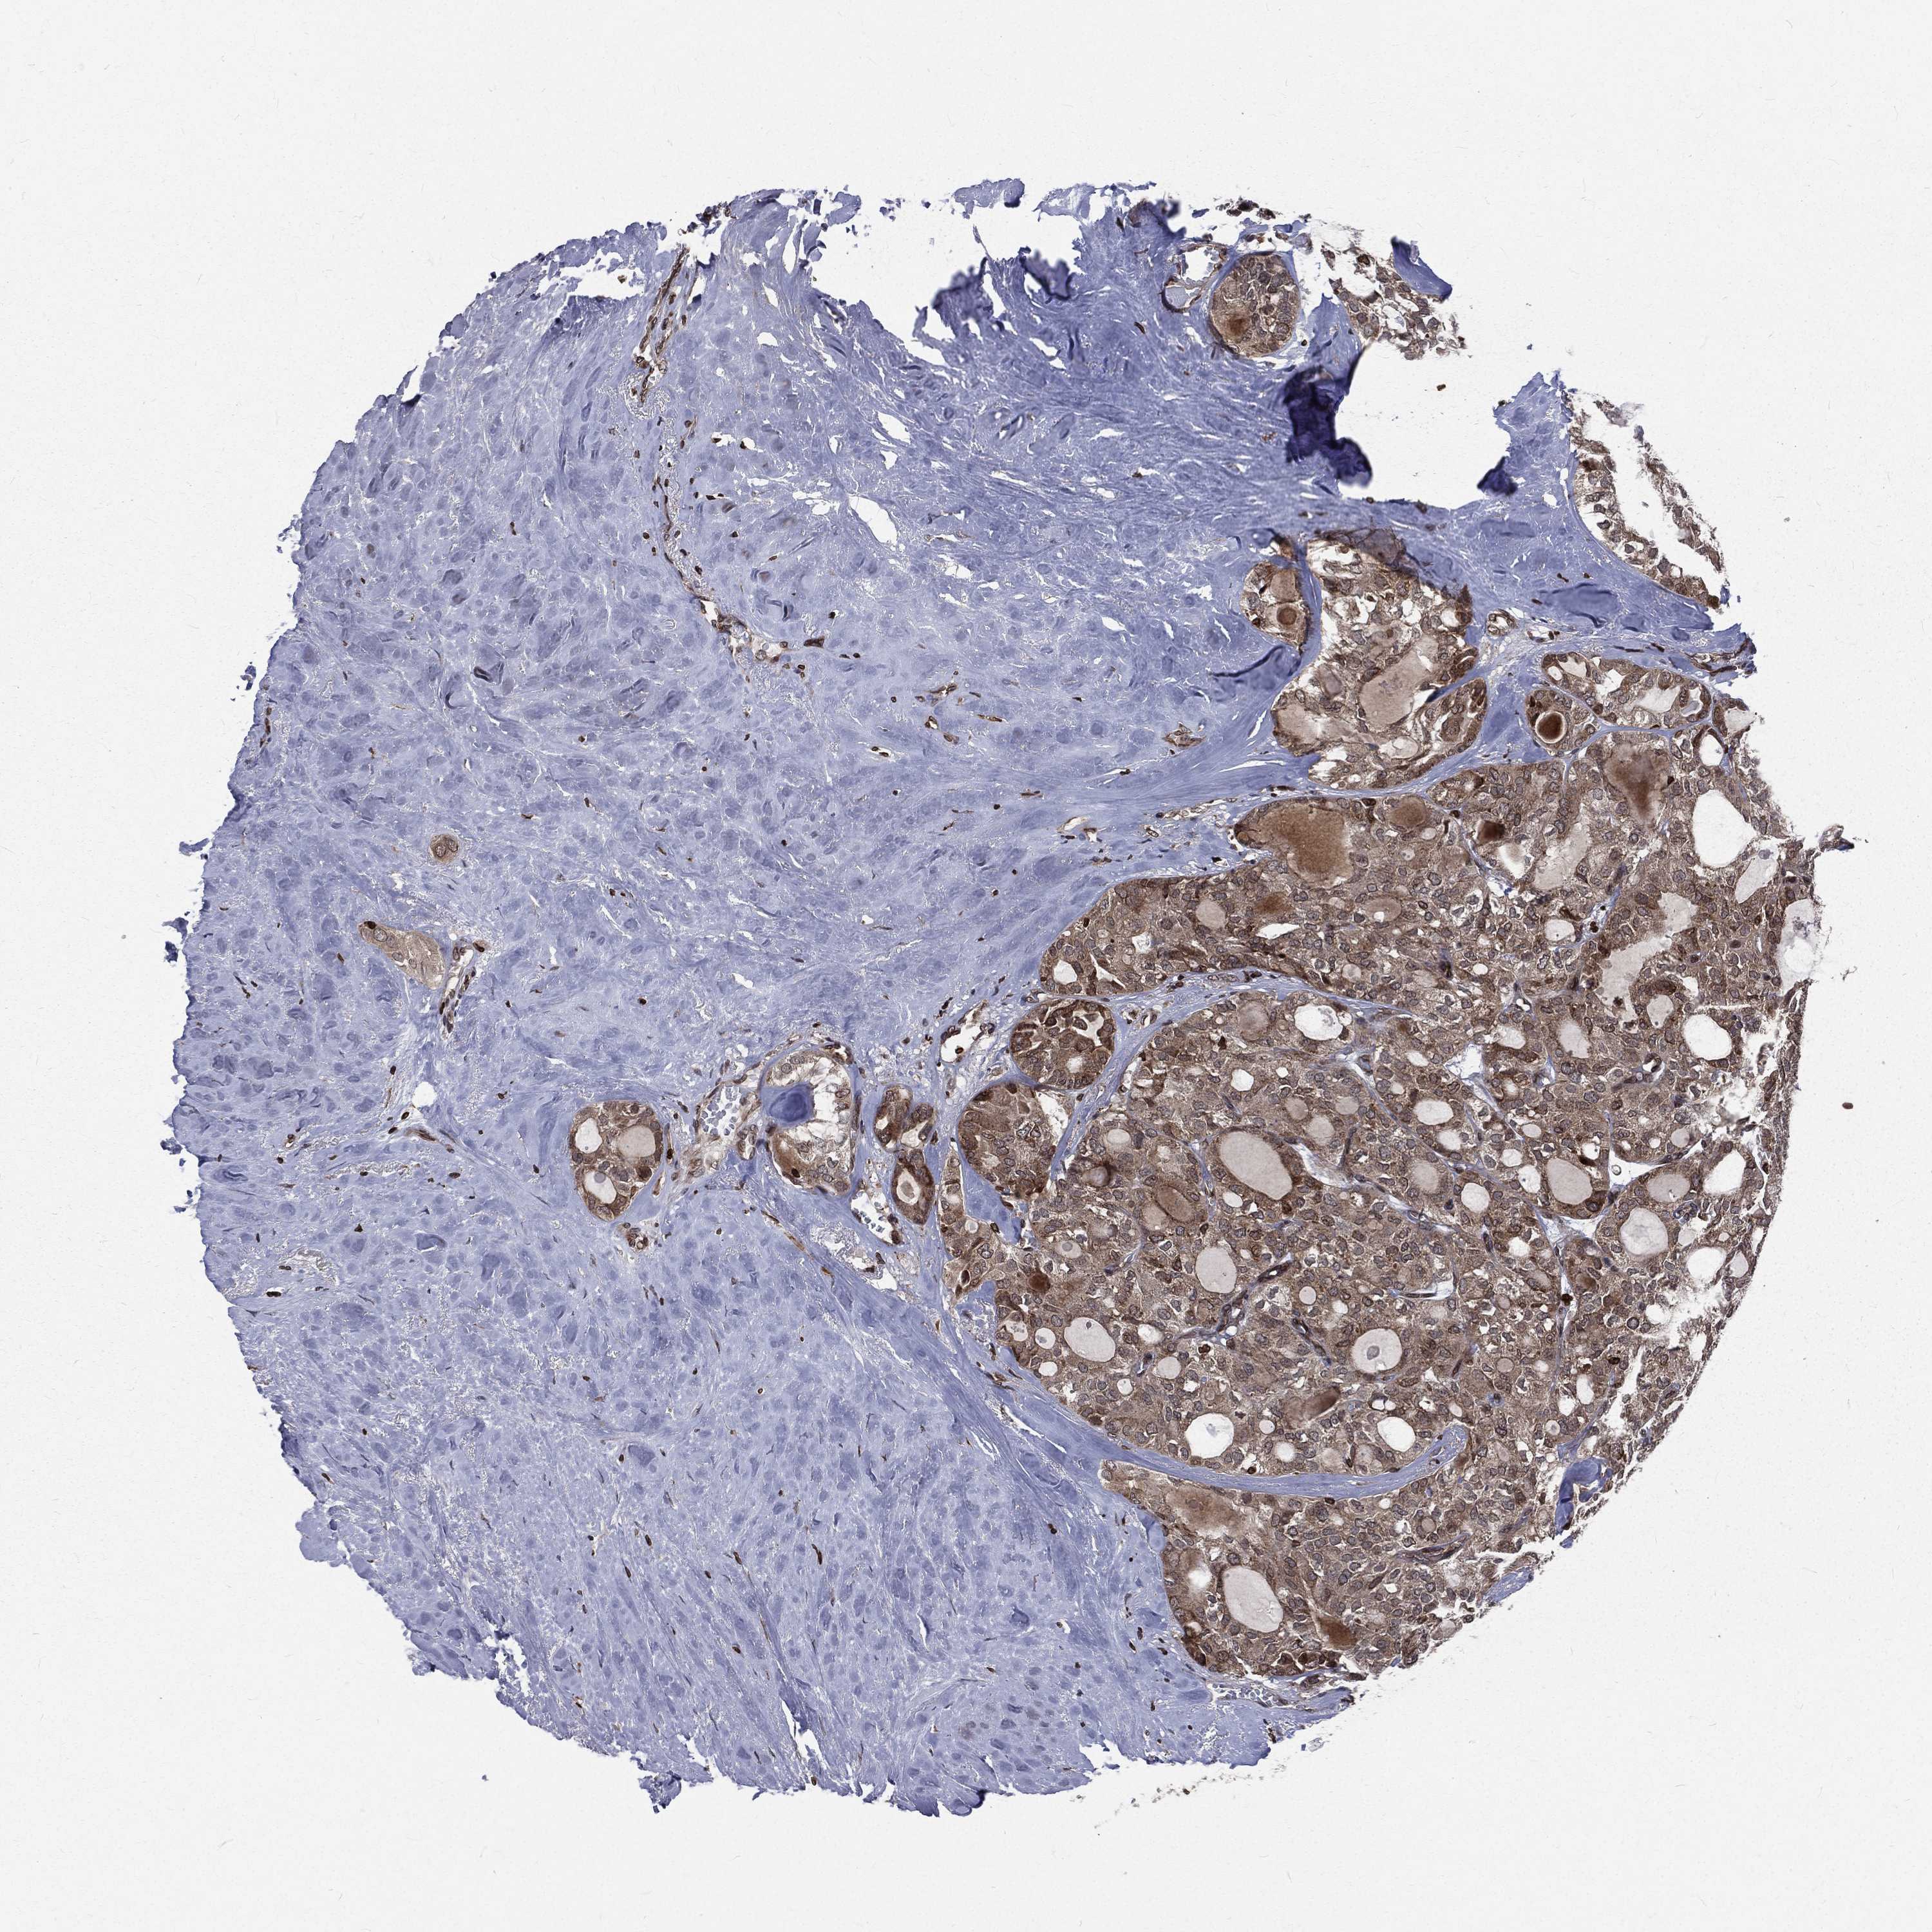

THYROID CANCER - Protein expressioni

A mouse-over function shows sample information and annotation data. Click on an image to view it in a full screen mode. Samples can be filtered based on level of antibody staining by selecting one or several of the following categories: high, medium, low and not detected. The assay and annotation is described here.

Note that samples used for immunohistochemistry by the Human Protein Atlas do not correspond to samples in the TCGA dataset.

Antibody stainingi

Antibody staining in the annotated cell types in the current human tissue is reported as not detected, low, medium, or high, based on conventional immunohistochemistry profiling in selected tissues. This score is based on the combination of the staining intensity and fraction of stained cells.

Each image is clickable and will lead to virtual microscopy that enables deeper exploration of all samples and also displays staining intensity scores, fraction scores and subcellular localization as well as patient and tissue information for each sample.

Antibody HPA049840

Antibody HPA062236

Staining

High

Medium

Low

Not detected

Intensity

Strong

Moderate

Weak

Negative

Quantity

>75%

75%-25%

<25%

None

Location

Nuclear

Cytoplasmic/membranous

Cytoplasmic/membranous,nuclear

Papillary adenocarcinoma, NOS

Follicular adenoma carcinoma, NOS